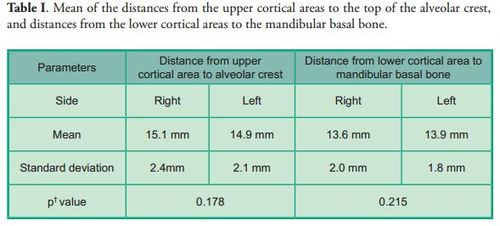

The distance from the upper and lower cortical areas of the mental foramen to the alveolar crest and the mandibular basal bone respectively was measured. No statistically significant differences were found between the right and left sides in either measurement (p*0.178), (p*0.215) (Table I).

The distance from the upper and lower cortical areas of the mental foramen to the alveolar crest and the mandibular basal bone respectively was measured. No statistically significant differences were found between the right and left sides in either measurement (p*0.178), (p*0.215) (Table I).

The distance from the lower cortical area of the mental foramen to the mandibular basal bone was (13.6 mm ± 2.0 mm) and (13.9 mm ± 1.8 mm) on the right and left sides respectively, which, on average, is consistent with the results of other studies (4, 13, 14).

The distance from the lower cortical area of the mental foramen to the mandibular basal bone was (13.6 mm ± 2.0 mm) and (13.9 mm ± 1.8 mm) on the right and left sides respectively, which, on average, is consistent with the results of other studies (4, 13, 14).

The distances from the upper and lower cortical areas of the mental foramen to the alveolar crest and the mandibular basal bone respectively were analyzed, as well as the size of the hole on the transaxial cut. There we considered the distance between the upper and lower cortical areas of the structure, and the measurements were classified into ranges (Figures 1 and 2).

The distances from the upper and lower cortical areas of the mental foramen to the alveolar crest and the mandibular basal bone respectively were analyzed, as well as the size of the hole on the transaxial cut. There we considered the distance between the upper and lower cortical areas of the structure, and the measurements were classified into ranges (Figures 1 and 2).